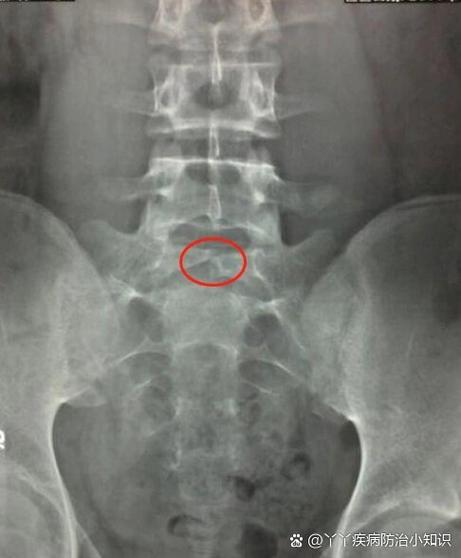

隐形脊柱裂。

“隐形”是相对于“显性脊柱裂”(或称“开放性脊柱裂”)而言的,显性脊柱裂通常伴有脊膜或脊髓通过脊柱缺损处膨出,形成包块,非常明显,而隐形脊柱裂是指椎弓骨性闭合不全,但表面的皮肤通常是完整的,没有可见的包块,它被称为“隐形”,这使得它更容易被忽略。

- 明确诊断:医生通常会进行详细的体格检查,并安排MRI(磁共振成像)检查来明确诊断,MRI可以清晰地显示脊髓、神经根和脊柱的解剖结构,是诊断隐形脊柱裂的“金标准”,有时也会使用X光或B超作为初步筛查。